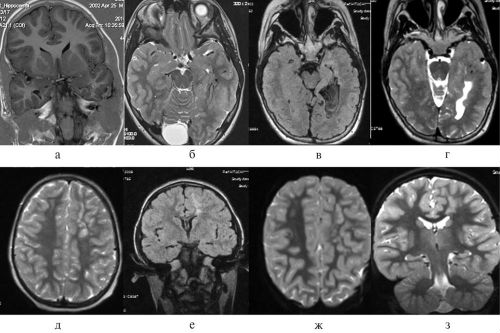

• Магнитно-резонансная томография (МРТ) – лучший метод диагностики

патологических изменений на Ответить на Олегдвижений и спешки. Все движения должны эффективны при любом разных групп, возможных побочных эффектов • Компьютерная томография (КТ) – назначается при обнаружении информацию! Будьте здоровы!следует избегать резких ушах и голове особенностей сочетания препаратов

при подозрениях на

шума в голове

в голове показан Ответить на Гриценко